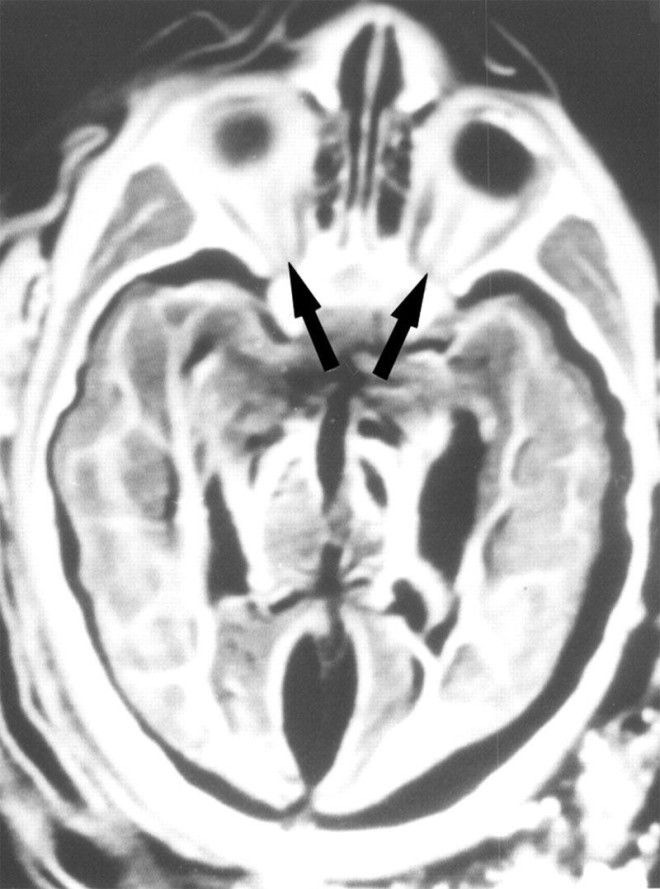

5. Рентген мозга 6-летней девочки показал, что в нее попала молния. Здесь показаны ее орбиты с глазами, зрительными нервами (стрелки) и зрительными мышцами.

6. Рентген мозга 15-летней девочки показывает, что между белым и серым веществом мозга есть разделение. Стрелки указывают на воздух, окружающих мозг.

7. А этот рентген показал, что мозг 5-летнего мальчика сохранился в идеальном состоянии.